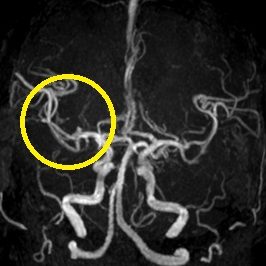

超急性期脳梗塞に対する血栓溶解療法(t-PA治療)

ろれつ困難と左半身重度麻痺のため当院に救急搬送となった患者様に対し、発症2時間30分でt-PAの投与を開始。t-PA開始1時間半後に左麻痺とろれつ困難は回復し始め、翌日には症状は消失。t-PA後のMRA検査で閉塞血管の完全再開通を認め、発症から2週間後に神経症状なく退院。

(来院時MRA検査画像)